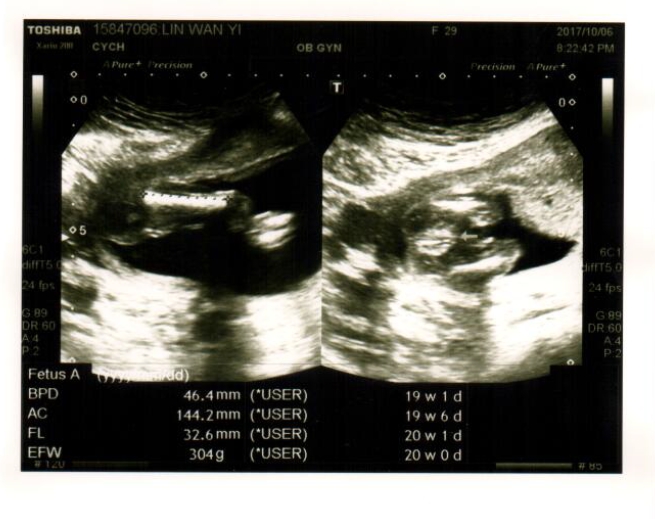

「胎兒看起來偏小,有做過什麼檢查嗎?羊膜穿刺、非侵入性晶片....」

產檢結束,我腦海中不斷想著王醫師說胎兒偏小那段話,回想去懷孕以來因為工作忙碌和交際應酬都不太早睡,又有時忙到沒時間吃飯,不禁擔心了起來,開始上網查訊胎兒偏小的資訊(強迫症上身了!)

除了睡眠和飲食以外,胎兒偏小和生長遲緩的狀況大部分似乎發生在唐氏症寶包身上,又胎動較少不明顯也是其一觀察的因素,孩子的胎動和上胎姐姐一樣,我並不太常能感受到強烈的胎動...天哪,我簡直要把自己嚇傻了,尤其回想王醫師問羊膜穿刺和非侵入性晶片等檢查,我一樣都沒做,且高層次超音波是測不出染色體異常的,在這次產檢之後我真的有點擔心,但又不時要告訴自己放寬心,順其自然。

20W,把你養胖胖,要好好長大好嗎。